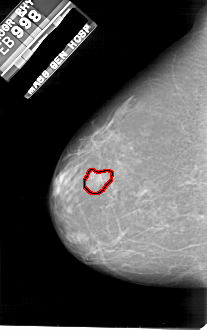

A_1811_1.LEFT_CC

FILE: A_1811_1.LEFT_CC.OVERLAY

TOTAL_ABNORMALITIES 1

ABNORMALITY 1

LESION_TYPE MASS SHAPE IRREGULAR MARGINS MICROLOBULATED

ASSESSMENT 4

SUBTLETY 2

PATHOLOGY BENIGN

TOTAL_OUTLINES 1

BOUNDARY